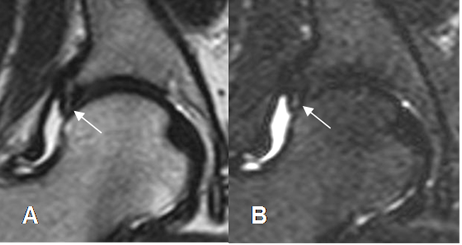

Fig 110. Lesión del cartílago.

A: ArtroRM sagital y B: ArtroRM axial en STIR. Presencia de contraste dentro del cartílago acetabular, por lesión.